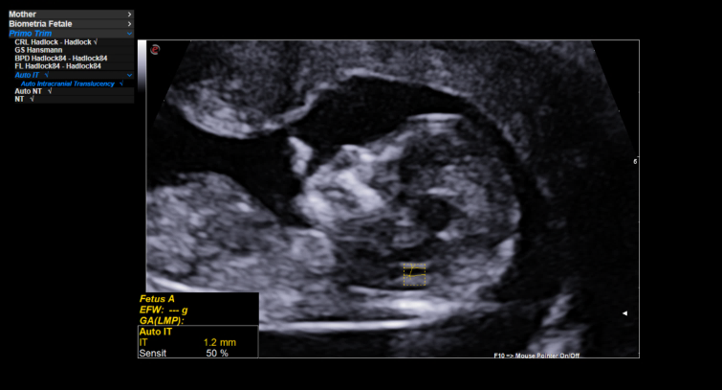

AutoNT – Automatic measurement of the Nuchal Translucency (NT)

Auto IT – Automatic measurement of Intracranial Translucency (IT)